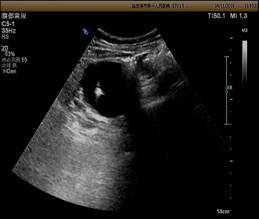

见图例

肾囊肿大小 两个月复查

治疗前在超声引导下选择穿刺点,然后将穿刺针的最短路径进入穿刺部位,抽出囊内液体,注入硬化剂,冲洗保留,破坏囊壁细胞,防止继续分泌液体。

整个过程均有实时动态的超声图像,清晰显示病灶,准确引导穿刺,全程进行监控,避免损失周围组织器官,巧妙地避开病灶周围血管,安全准确。(不用开刀就可治愈哦)